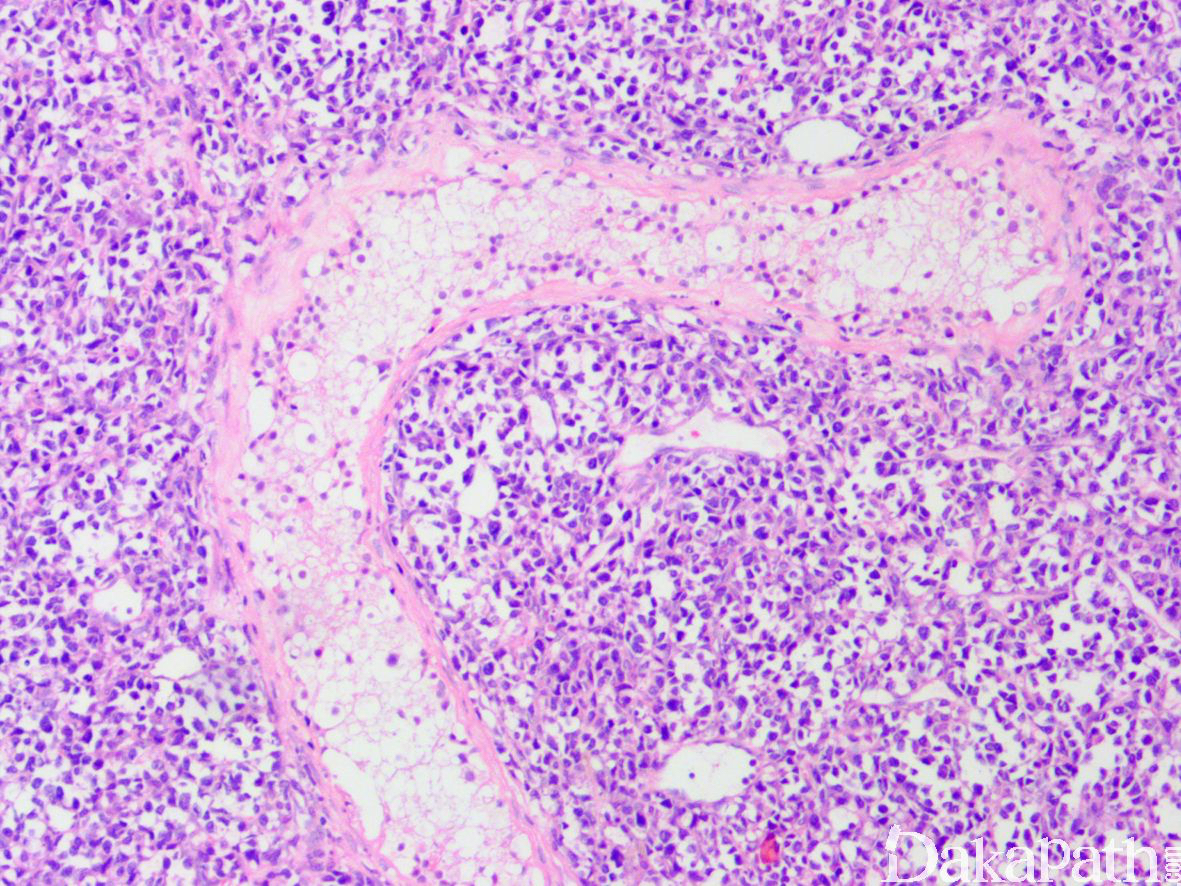

- 镜下异型淋巴细胞弥漫浸润,常见凝固性坏死及细胞凋亡;

- 曲细精管及血管浸润常见,有时可累及附睾;